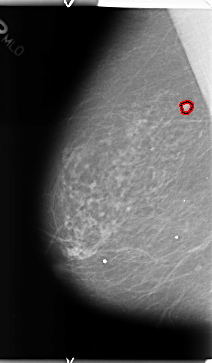

B_3126_1.RIGHT_MLO

RIGHT_MLO LINES 4712 PIXELS_PER_LINE 2752 BITS_PER_PIXEL 12 RESOLUTION 50 OVERLAY

FILE: B_3126_1.RIGHT_MLO.OVERLAY

TOTAL_ABNORMALITIES 1

ABNORMALITY 1

LESION_TYPE MASS SHAPE ROUND MARGINS CIRCUMSCRIBED

ASSESSMENT 3

SUBTLETY 4

PATHOLOGY BENIGN

TOTAL_OUTLINES 1

BOUNDARY